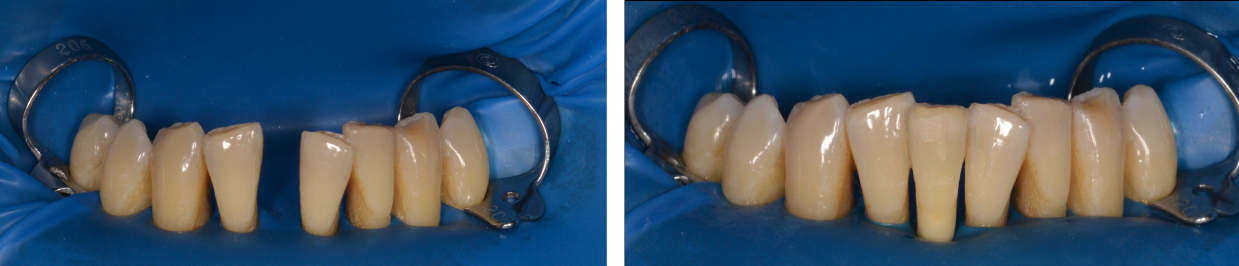

După imobilizare, dinților li se aplică terapia parodontală uzuală, pacientul fiind monitorizat la intervale regulate de timp. Este o soluție viabilă atât timp cât și pacientul menține o igienă riguroasă a zonei respective, foarte important fiind să existe zone libere pentru igienizarea interdentară. Unele cazuri implică păstrarea sistemelor de imobilizare pe parcursul mai multor ani de zile, pacienții fiind deschiși la metode minim invazive rapide, acestea incluzând soluțiile finale protetice sau implantare. (Fig. 5.4.6, 5.4.7)